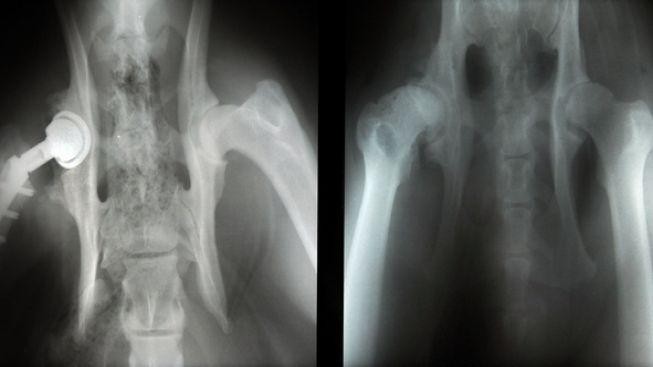

Artrózu mají v ČR dva miliony lidí, hlavní prevencí je pohyb

zdroj: Profimedia

Artrózu mají dva miliony Češek a Čechů, postihuje každého pátého člověka nad 45 let a 60 procent lidí starších 65 let. I proto jsou reklamní preparáty na klouby oblíbeným vánočním dárkem pro seniory.